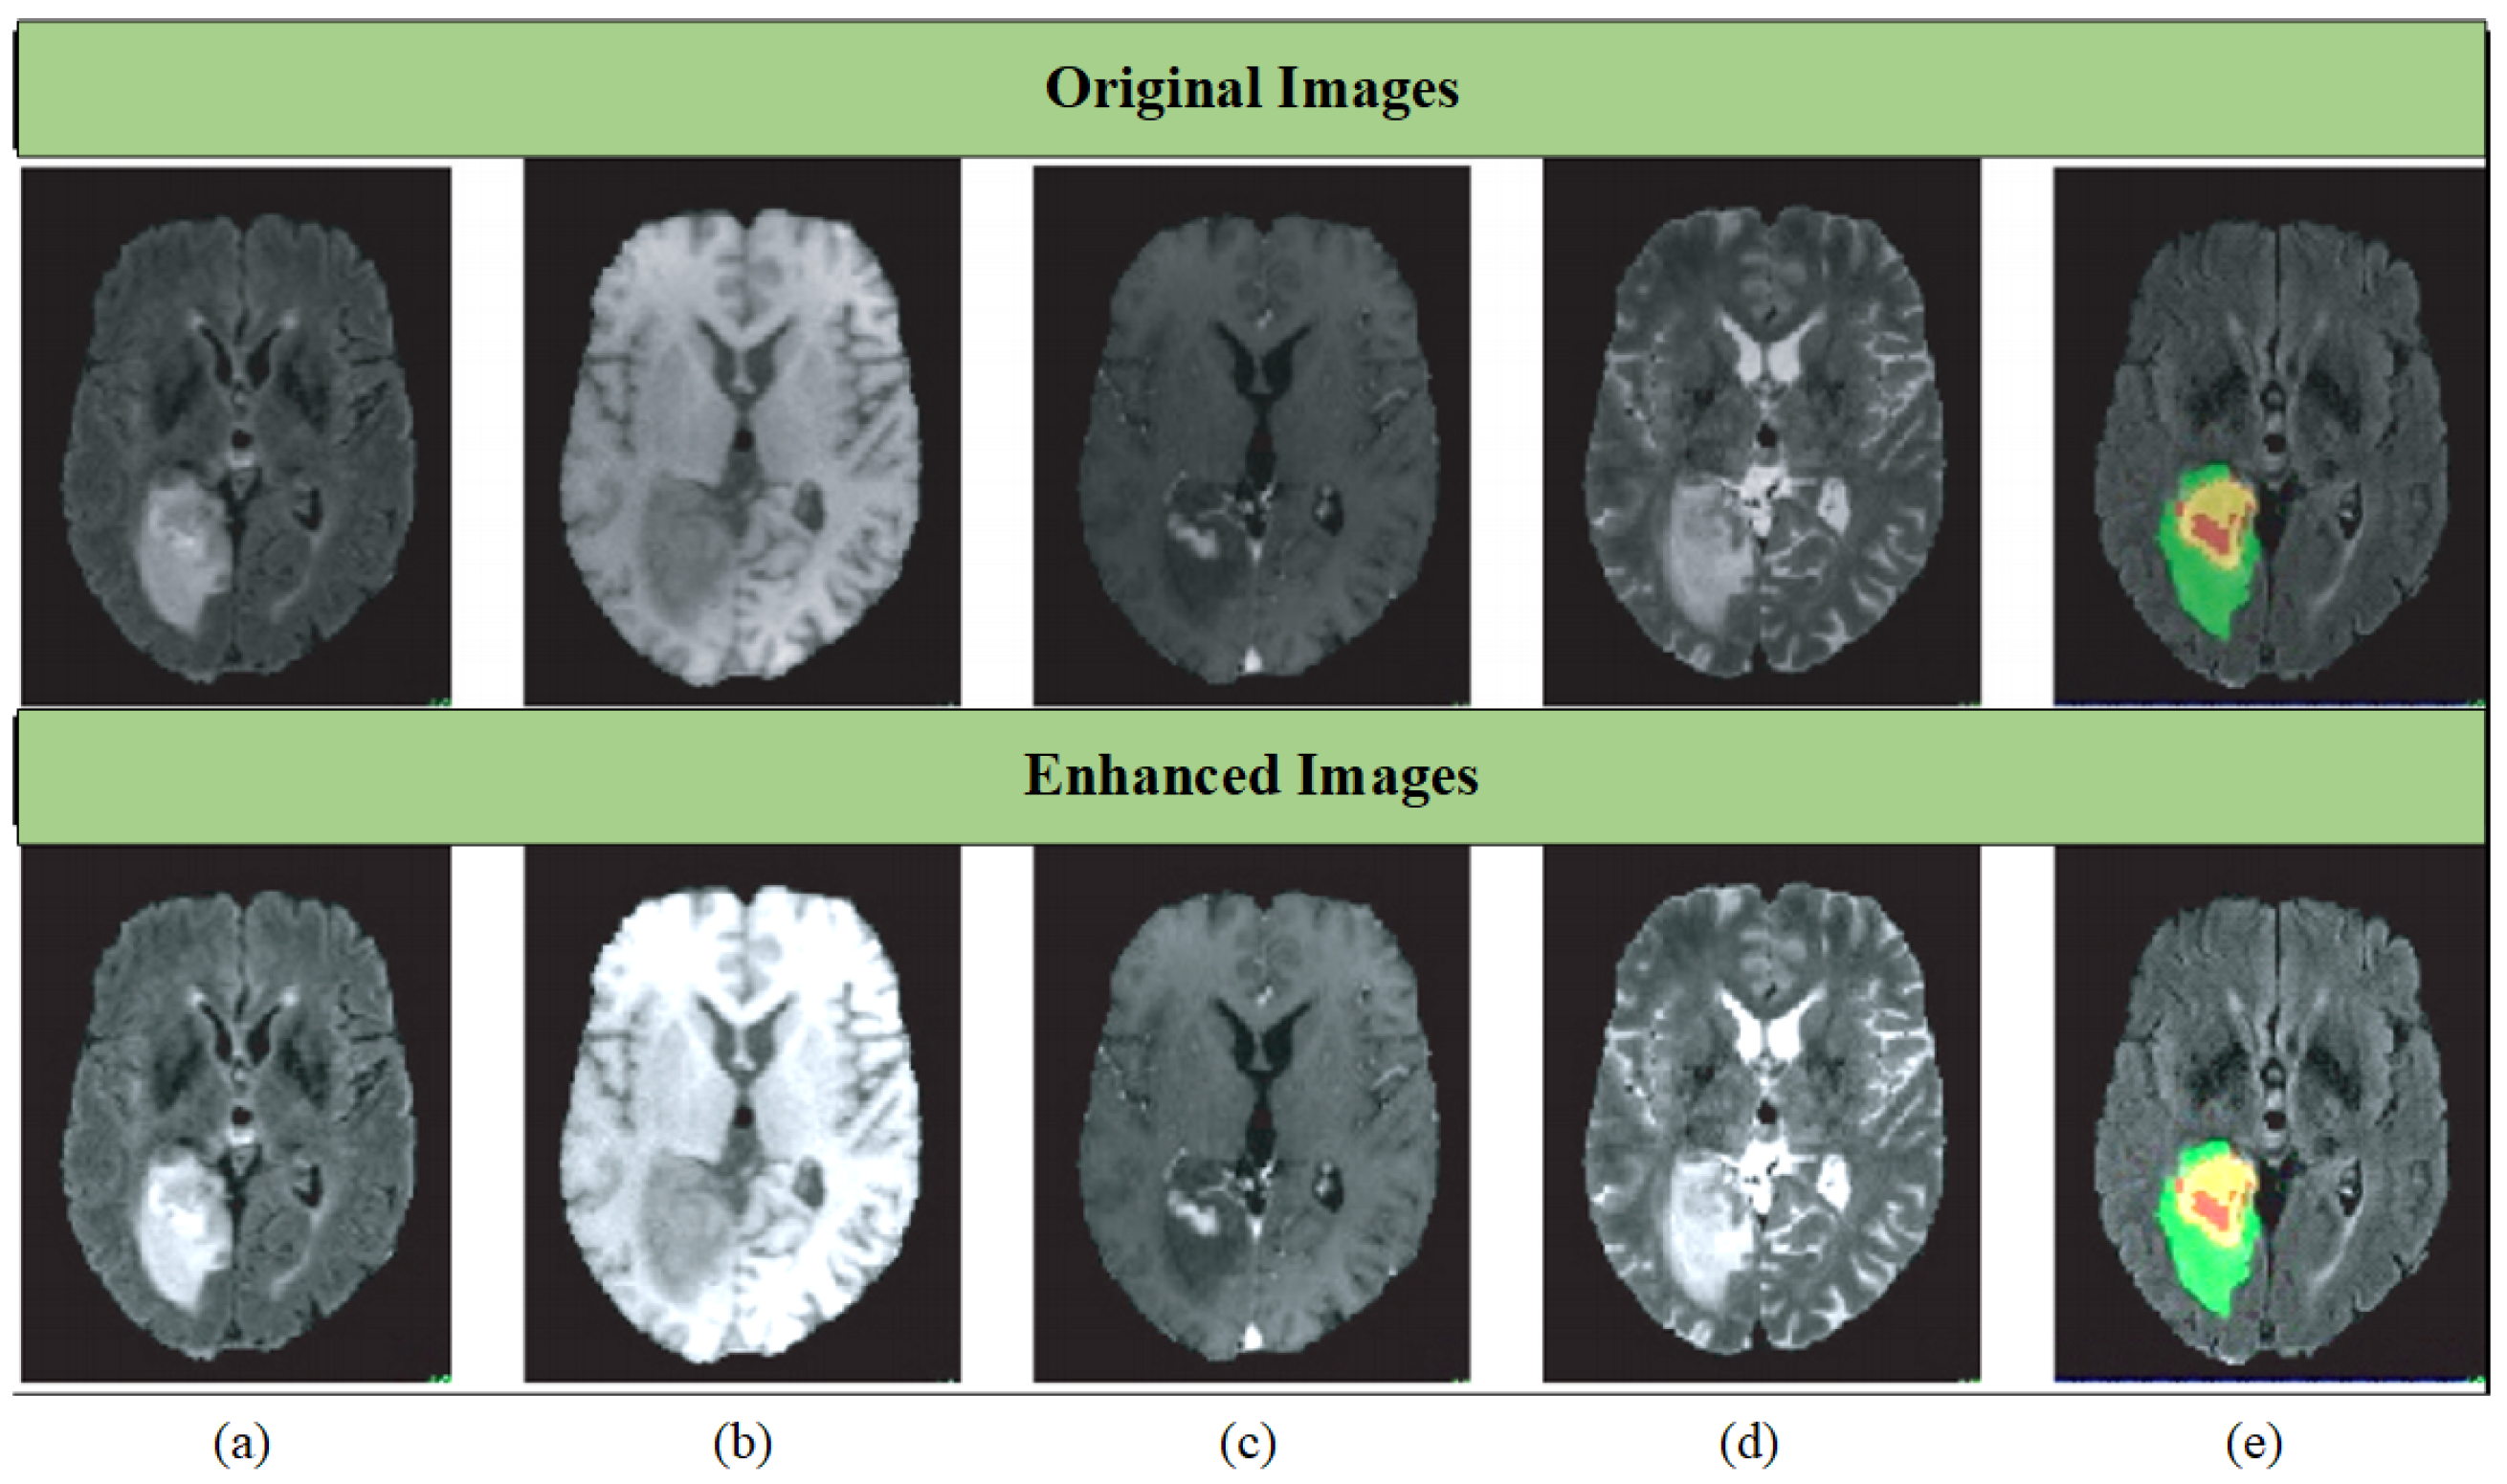

where signifies the initial MRI image, represents the MRI image that is processed using the logarithmic transformation, is the image adjusted using the straightforward exponential equation, is the combined image subsequent to the application of the advanced logarithmic-based image processing model, is the image after being refined using the updated cumulative distribution function based on hyperbolic secant distribution, and is the image subsequent to adjustment using the linear scaling technique. To provide a visual representation, Figure 3 showcases original and enhanced MRI brain tumor images. Within this image, distinct colors demarcate different tumor types: red signifies necrotic and non-enhancing tumor regions; green highlights peritumoral edema regions; and yellow delineates enhancing tumor regions. This color-coded approach aids in intuitive understanding and analysis.

Figure 3.

Visual results of original and adjusted images. (a) FLAIR, (b) T1, (c) T1ce, (d) T2, and (e) ground truth.